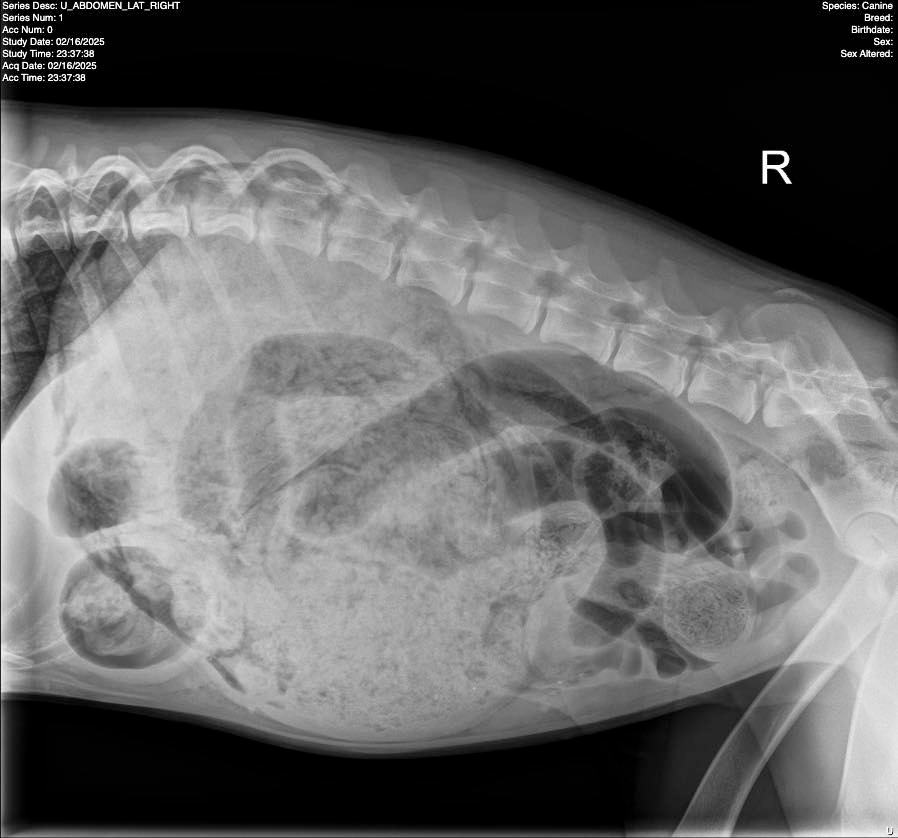

An X-ray soon revealed something completely unexpected. Luna’s stomach was packed with foreign objects, and her intestines were severely blocked.

“What we found was jaw-dropping: 24 socks, one scrunchie, two hair ties, one shoe insert, one small onesie (from her intestines!) and miscellaneous cloth pieces,” the hospital wrote on Instagram.

The clinic later posted X-ray images alongside a picture of the veterinarian posing with the incredible assortment of items removed from Luna’s stomach.